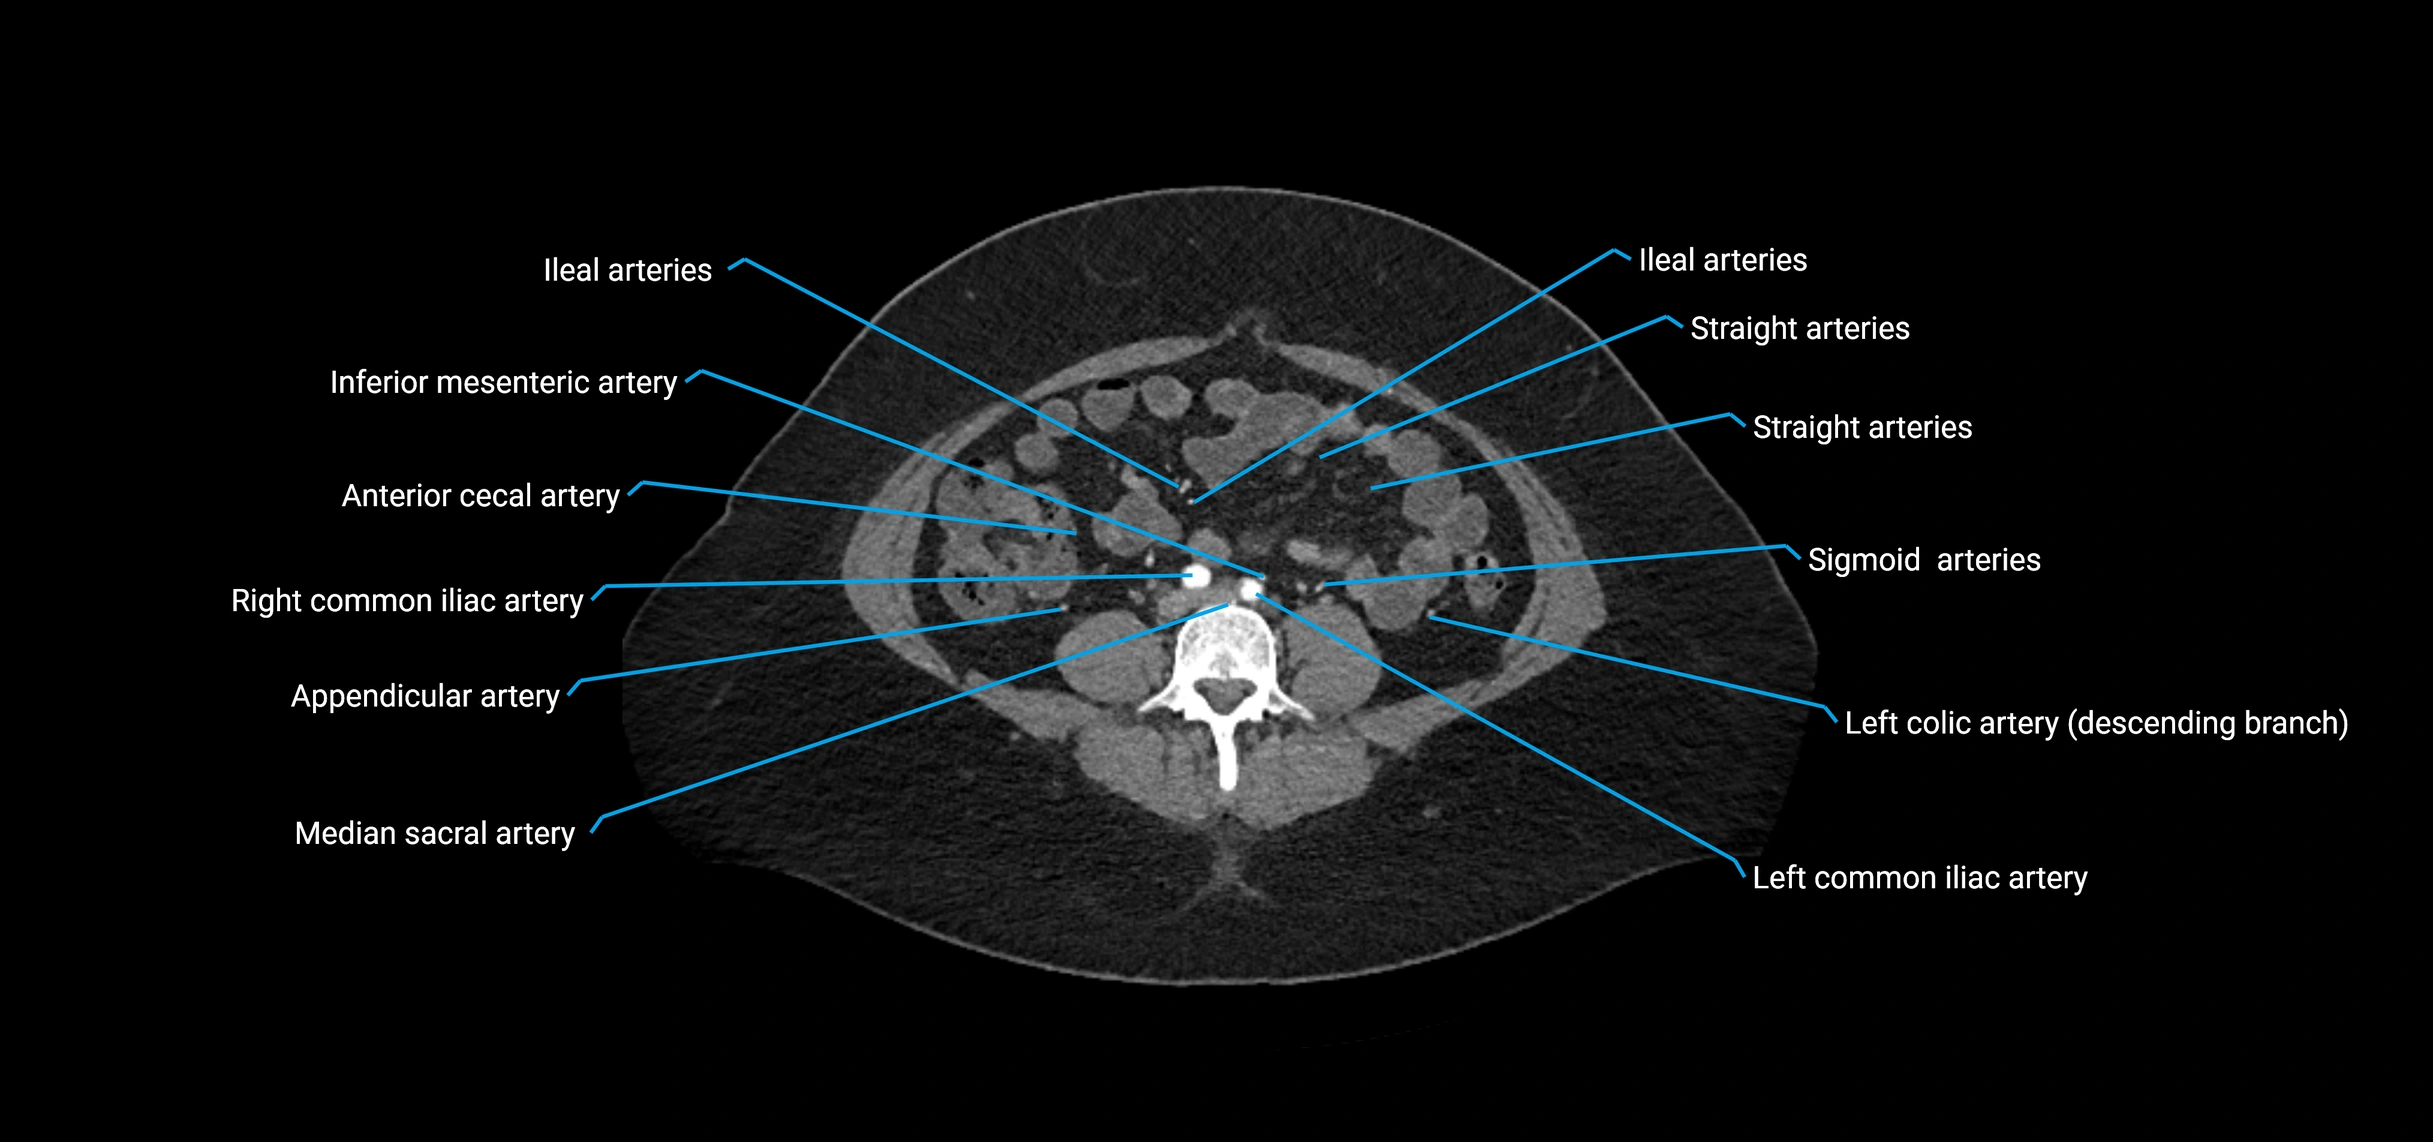

Contrast-enhanced CT (CTA):

• Gold standard for abdominal aortic imaging

• Provides excellent detail of lumen, wall, aneurysm, thrombus, and branch vessels

• Multiplanar and 3D reconstructions help in aneurysm measurement, stent graft planning, and dissection evaluation

• Detects acute rupture, traumatic injury, or occlusion with high sensitivity